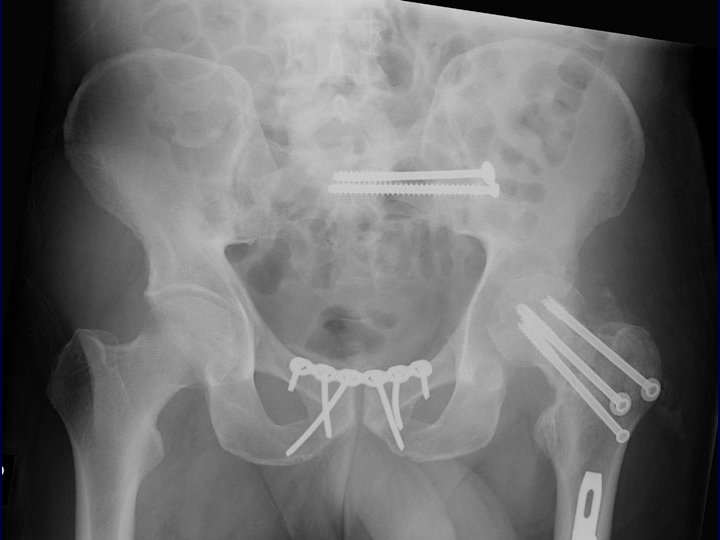

Immediate Percutaneous Fixation • From Chip Routt, MD